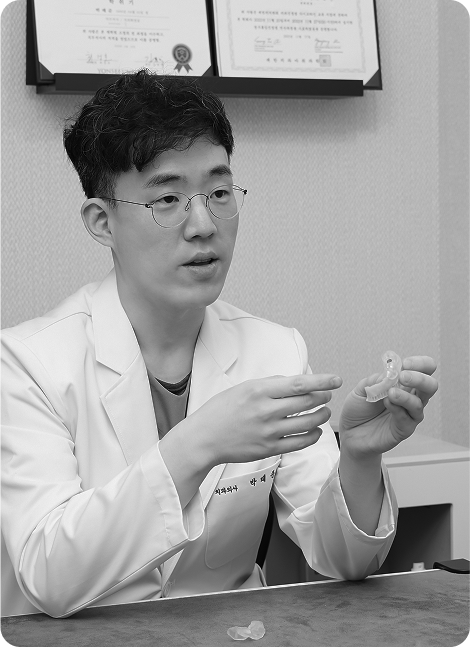

통합치의학과 전문의 대표원장이 시작부터 끝까지 맞춤케어 해드리겠습니다.

어려운 케이스일수록

자신 있습니다.

당뇨 · 고혈압 등 전신질환 수술을 받으신 분부터 재수술이 필요하신 분들까지.

원칙대로 진행한다면, 문제가 생길 수 없습니다.